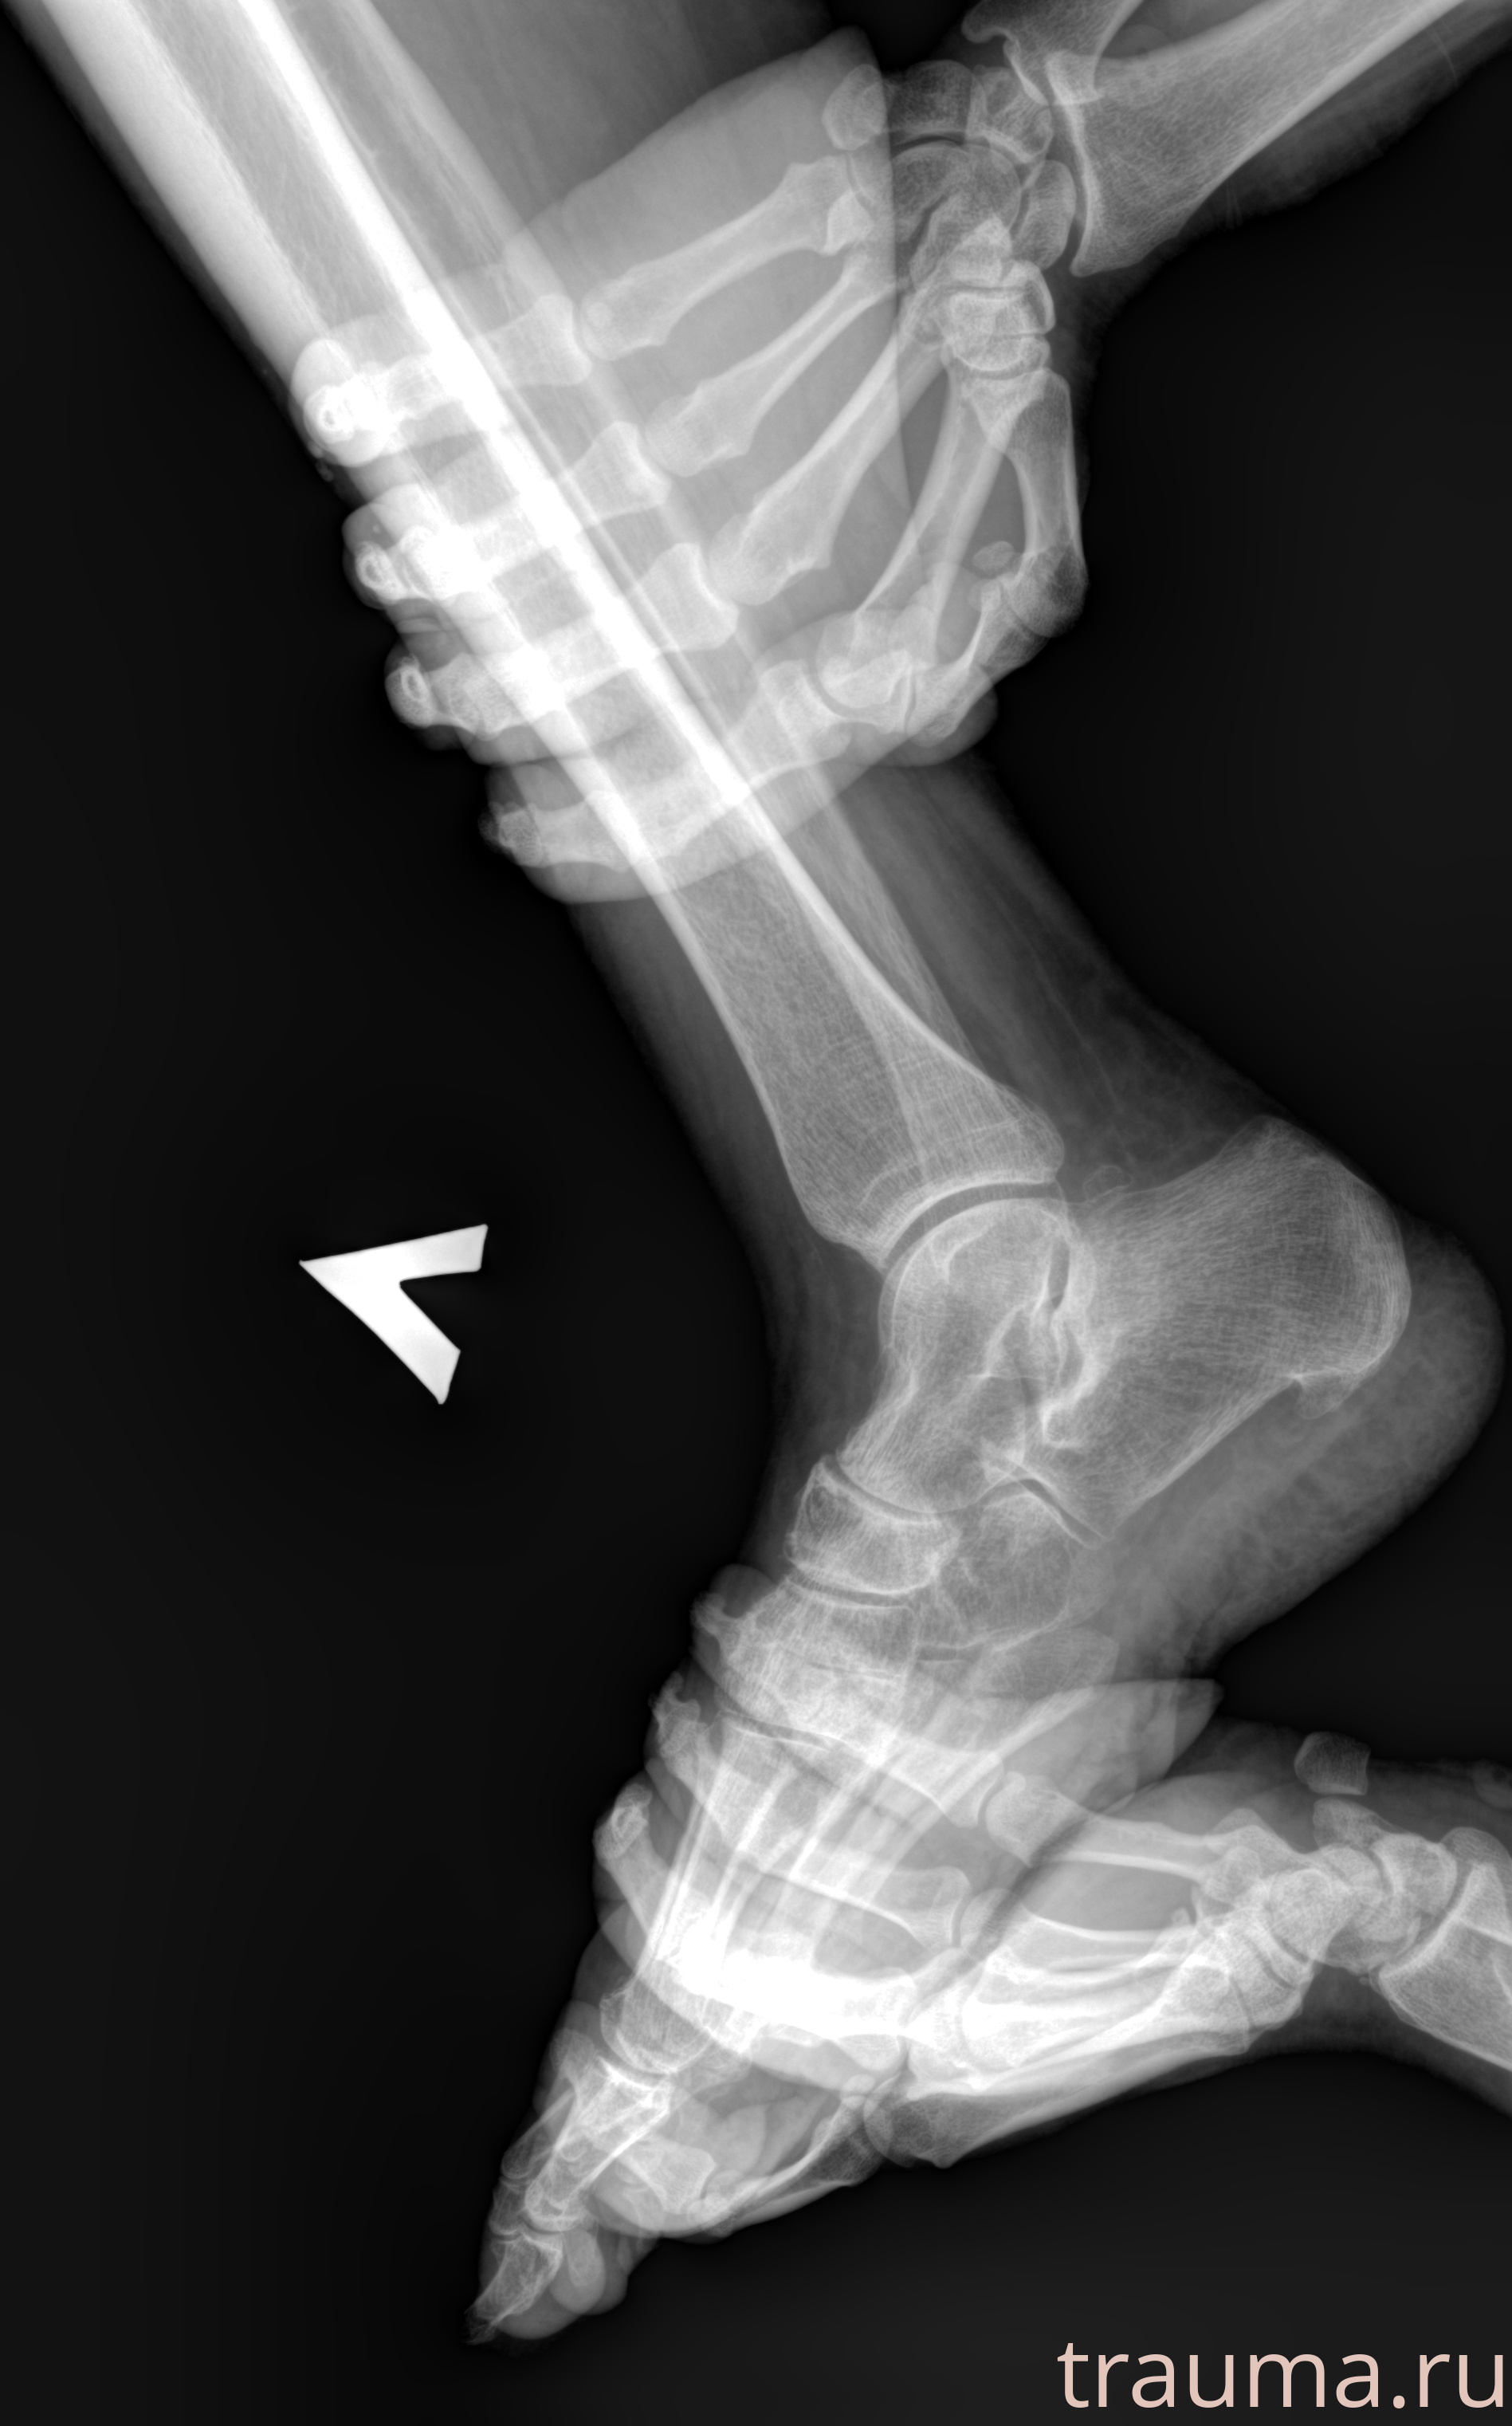

Рентген на дому: по вашему адресу приезжает врач-рентгенолог, травматолог-ортопед с мобильным рентгеновским аппаратом, проводит диагностику травмы или заболевания, делает необходимые рентгенограммы, дает рекомендации по дальнейшему лечению. Получить качественные снимки в домашних условиях возможно благодаря уникальной методике, разработанной МосРентген Центром для института  Склифосовского